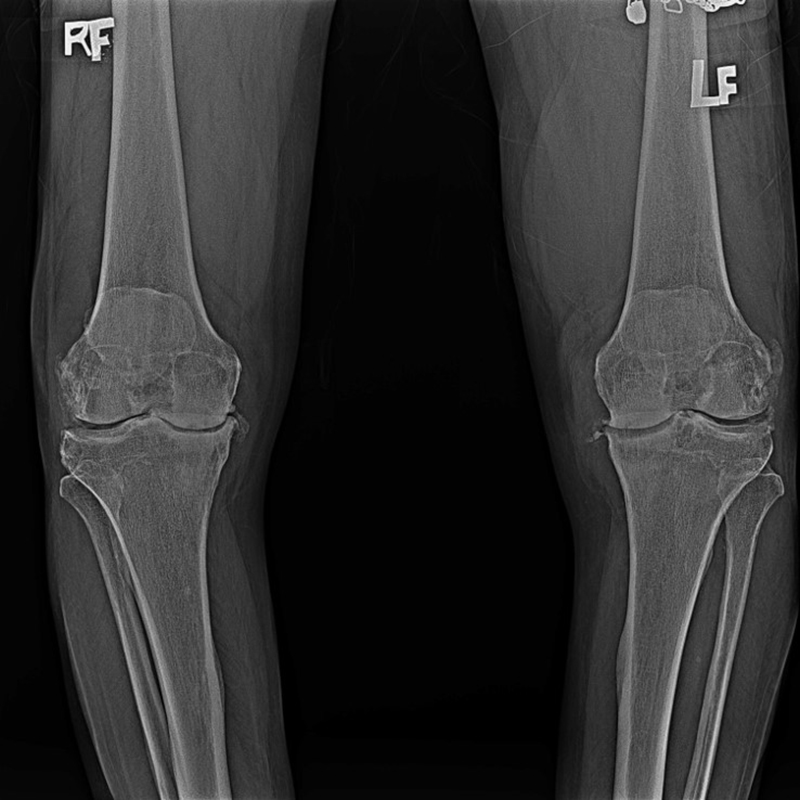

傳統全膝關節置換 首頁 案例分享 膝關節手術 傳統全膝關節置換 江女士 61歲 術前 術後 劉先生 83歲 術前 術後 70歲 柯先生 術前 術後 75歲 黃女士 術前 術後 77歲 羅女士 術前 術後